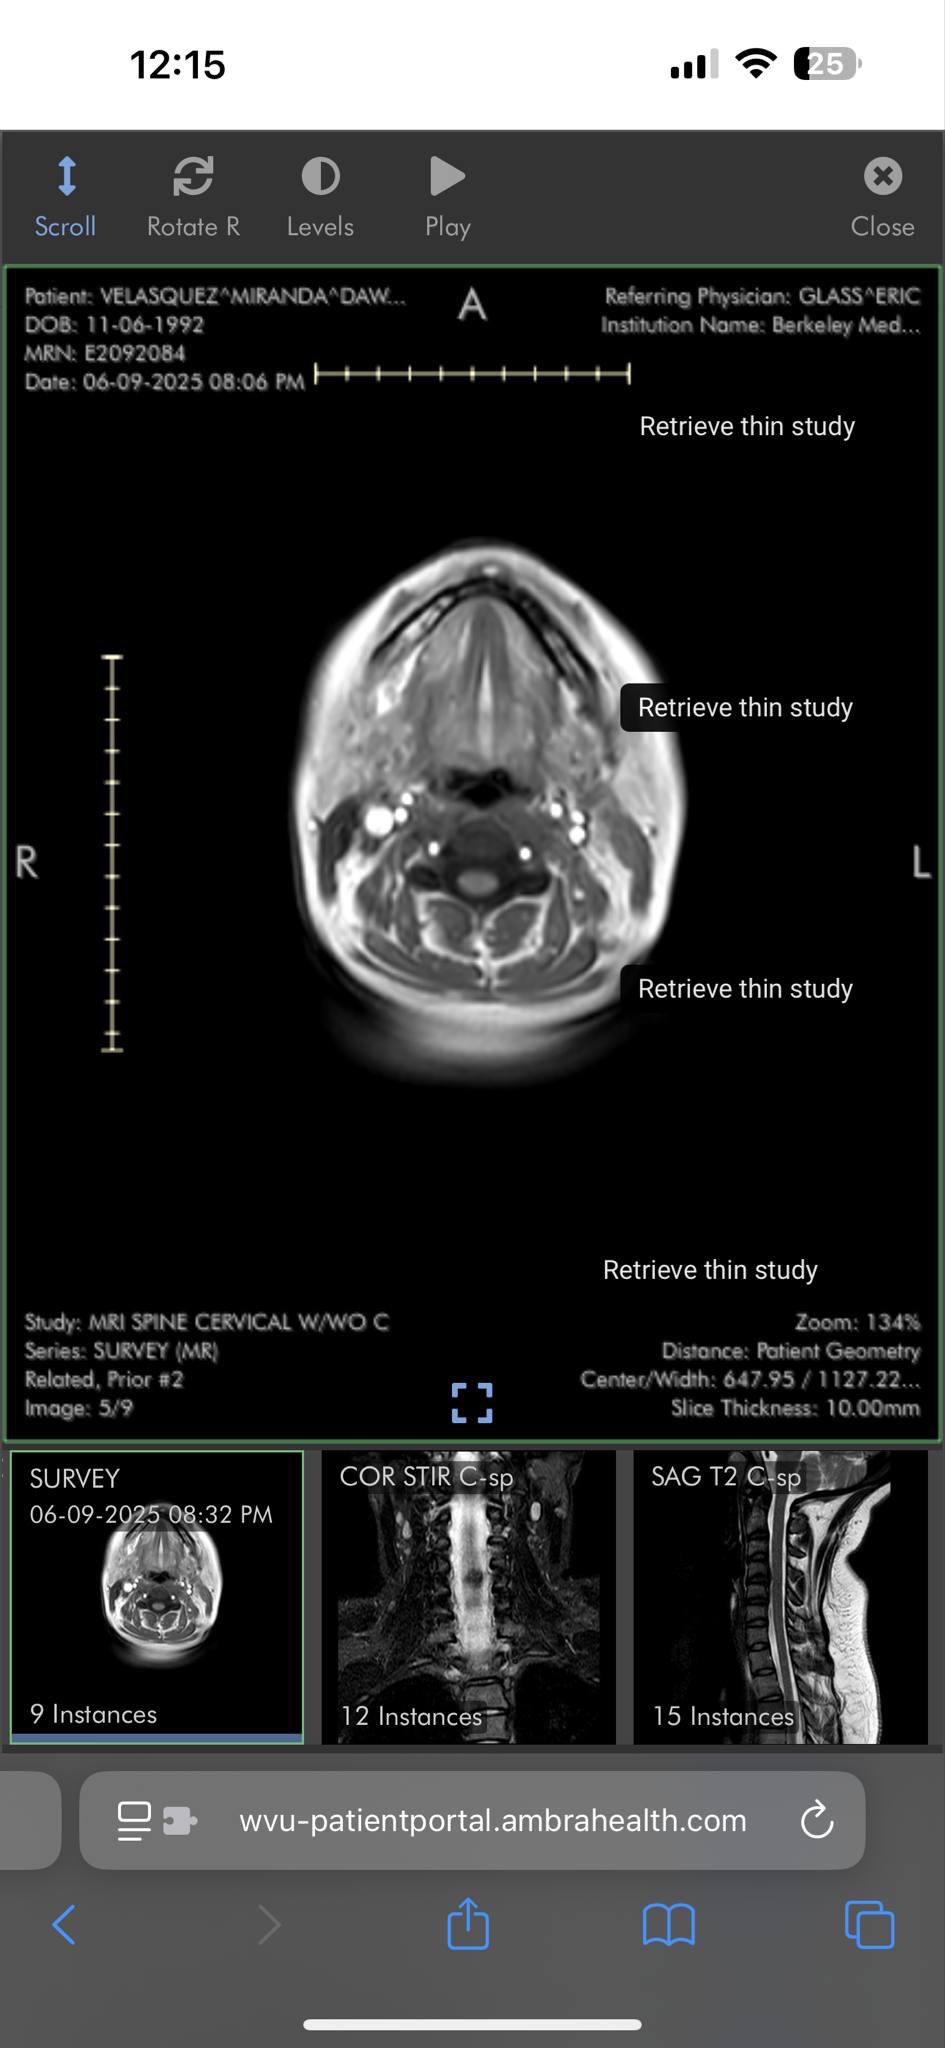

In addition to this, I was diagnosed with multiple sclerosis in 2020. MS is an unpredictable and often disabling disease that affects my daily life. Recently, on April 1, 2026, I received news that new lesions have developed, indicating progression of my condition. This makes Dari’s presence in our home even more critical, as he helps care for me and our children, especially on the days when my symptoms make it difficult to function.